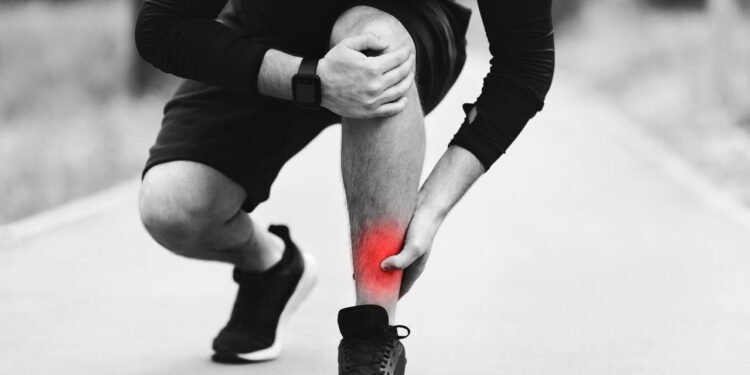

Entre os praticantes de esportes, especialmente aqueles que incluem corrida ou saltos em sua rotina, a dor na canela é um sinal que costuma gerar preocupação. Esse desconforto, que pode variar de uma leve ardência até uma dor mais intensa, é frequentemente associado à canelite. Apesar de ser bastante conhecida no universo esportivo, essa condição também pode afetar pessoas que estão começando a se exercitar ou que aumentaram recentemente a intensidade das atividades físicas, segundo a Clínica Avanttos.

A canelite é uma inflamação que acomete a região da tíbia, o osso localizado na parte frontal da perna. Os sintomas mais comuns incluem dor ao longo da canela, sensação de queimação e, em alguns casos, inchaço leve. O incômodo costuma aparecer durante ou após exercícios que envolvem impacto repetitivo, como correr, pular ou praticar esportes de quadra.

Nos estágios iniciais, a dor pode ser percebida apenas durante a atividade física, mas, se não houver cuidado, pode persistir mesmo em repouso. Em situações mais avançadas, a sensibilidade ao toque e a dificuldade para movimentar a perna também podem estar presentes.